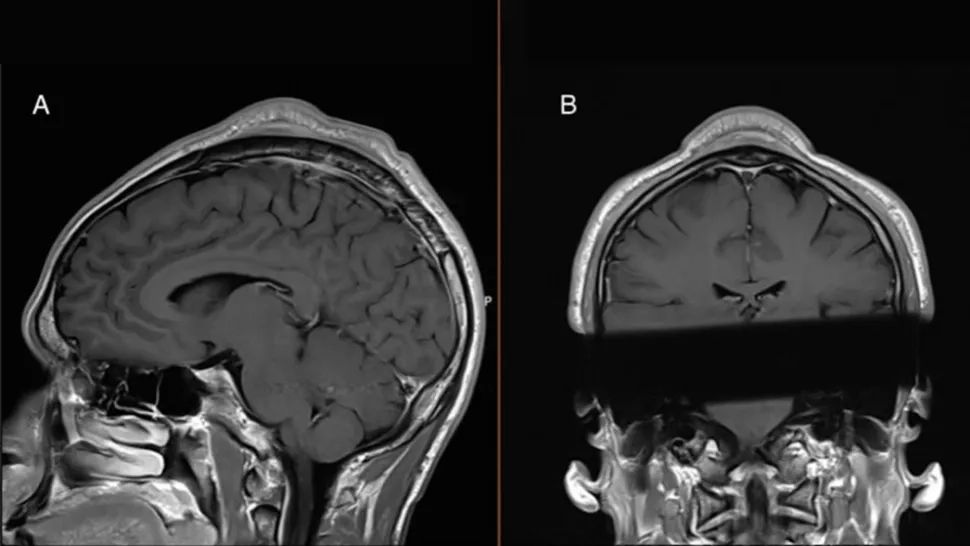

Un caz medical i-a surprins până și pe specialiști. În urma unei radiografii, aceștia au descoperit că unui împătimit al breakdanceului i-a apărut un guguloi în creștetul capului, ca urmare a numeroaselor rotiri pe cap, așa numitul procedeu "headspin", una dintre cele mai populare figuri în acest dans sportiv.

Un bărbat a dezvoltat „dul de breakdance” în vârful capului după ce a practicat în mod repetat headspins. Nodul bulbos de țesut, pe care medicii l-au îndepărtat chirurgical, devenise sensibil la atingere și avea dimensiunea cercului de cădere a părului, din cauza frecării cu podeaua.

Aceste umflături fără păr de pe cap sunt, de asemenea, numite în mod obișnuit „găuri de headspin (procedeul de rotire pe cap specific breakdance-ului)” sau, în limbaj de medicină sportivă, „sindrom de suprasolicitare a breakdancerului”.

„În ciuda faptului că aceste „găuri de headspin” sunt cunoscut în comunitatea breakerilor, este puțin documentat în literatura medicală”, au remarcat medicii într-o lucrare publicată într-o publicație de specialitate, citată de Live Scienece.

Pe baza rezultatelor lor, tratarea acestor umflături pe cap prin intervenție chirurgicală va deveni o procedură de rutină.